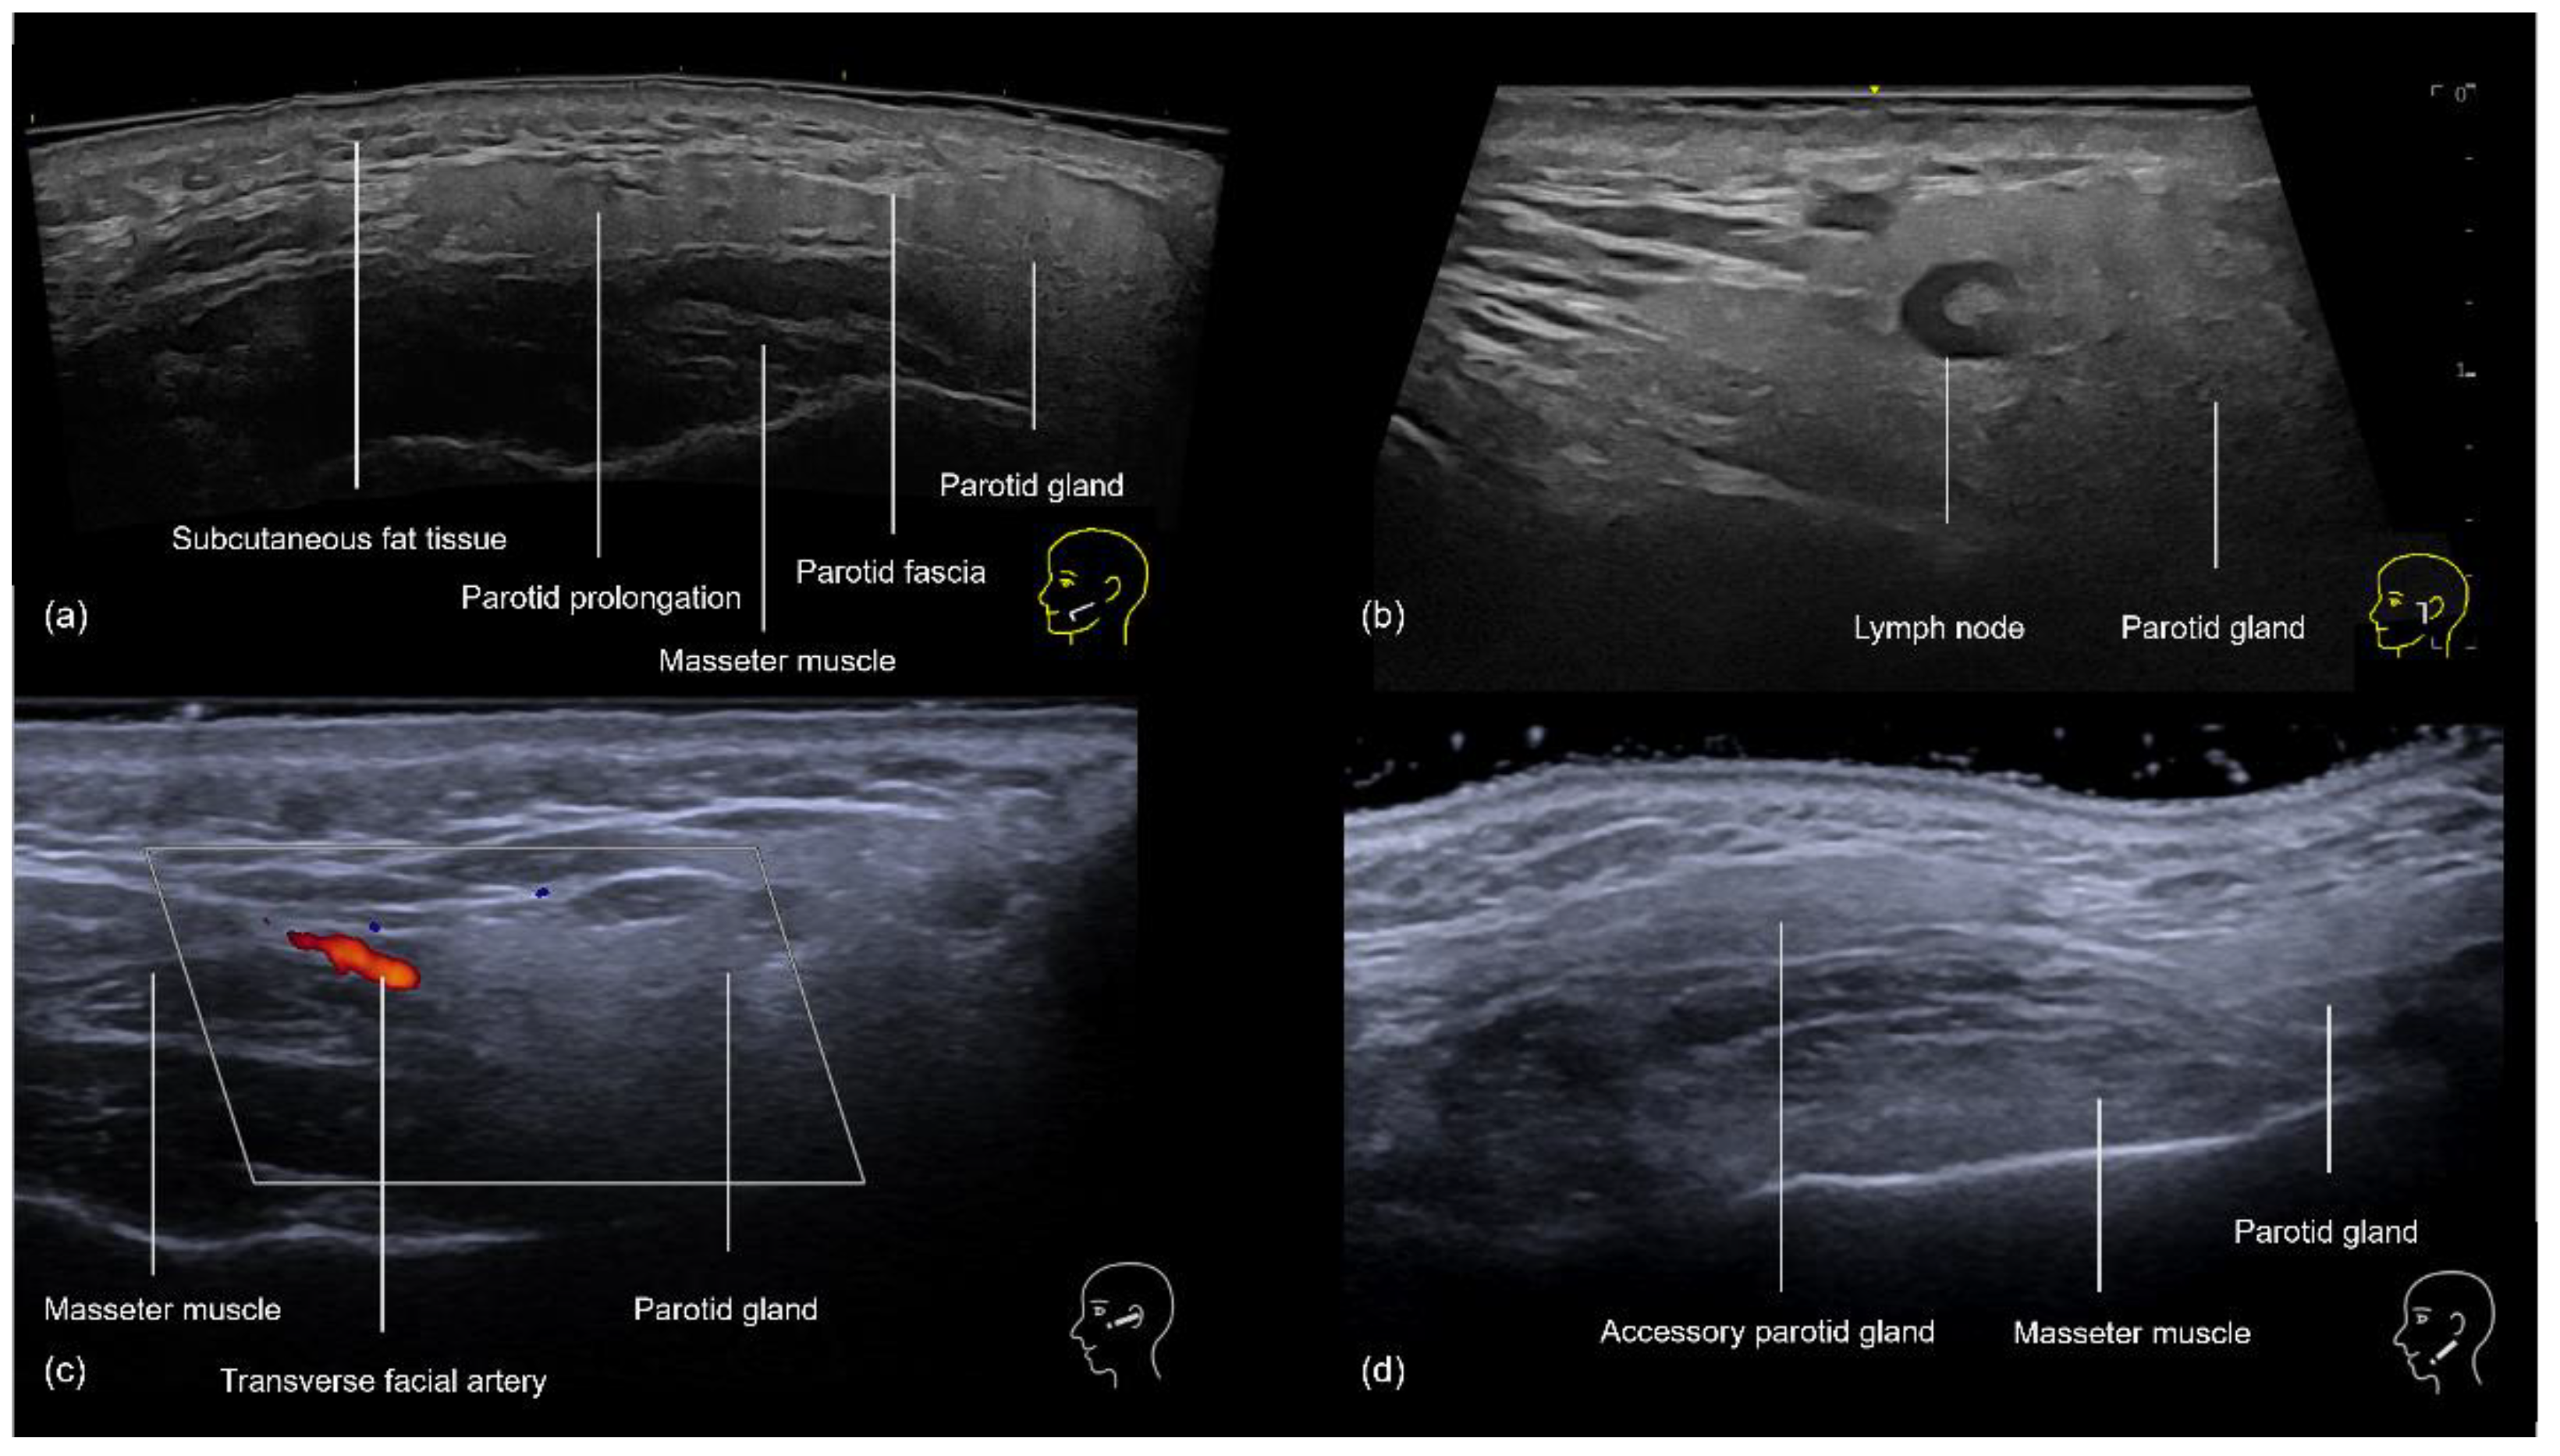

In the preauricular region, the sonographic anatomy is more complex due to the proximity of the parotid gland. The layers visible on ultrasound (Figure 12a–d) include the skin, subcutaneous fat, SMAS, transverse facial artery, parotid fascia, parotid gland, and masseter muscle [16]. The subcutaneous tissue is particularly thin in this area, often measuring between 2 and 4 mm, which increases the risk of inadvertently injecting filler into the parotid gland. This can lead to serious complications, including inflammation, abscess formation, and chronic parotitis [16]. Even if the filler is placed near the glands, there is still a chance of developing inflammation [17]. Additionally, anatomical variations such as accessory parotid glands (Figure 12d) or prominent anterior prolongations (Figure 12a) that cover the upper third of the masseter muscle should be carefully avoided to prevent these issues [16].

Figure 12.

US of the preauricular region layers. (a) Prominent anterior prolongation of the parotid gland. (b) A normal lymph node inside the parotid gland with a hyperechoic hilum (transverse panoramic and longitudinal view at 18 MHz, respectively). (c) Color Doppler highlighting the transverse facial artery emerging between the masseter muscle and the parotid gland. (d) Grayscale US demonstrating an accessory parotid gland superficial to the masseter muscle (transverse view at 18 MHz).